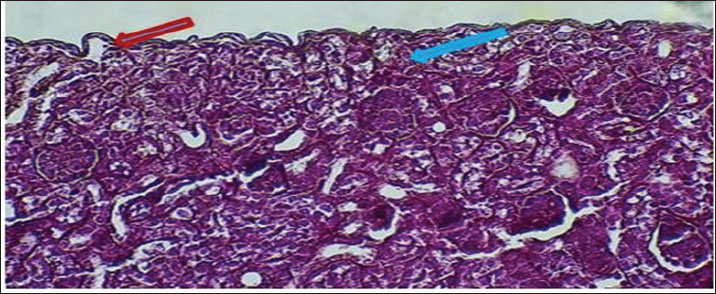

Figure 6 shows that the maturation of kidney tissue was visible on the later low-power H&E section of the 2-week-old hamster kidney compared with the 1-week specimen. The red arrow indicates how the renal cortex parenchyma is arranged, and the tubular regions are increasingly gathered and distinguished. Because the glomerulus was better developed, there was a clearer and bigger outline of the renal corpuscle. The yellow arrow marks the tubules that have been collected, and they now have distinct profiles and clear lines between epithelial cells, showing that urine concentration is starting and nephron structures are also dividing further. Figure 7 (Section Masson) implies that the capsule of the kidney cortex has received more fibrous support than in the previous stages. Columnar epithelial cells (marked by the blue arrow) were longer and better arranged in the inner part of the sac than they had been a week ago. The red or pink epithelial layer and the cytoplasmic structure were clearer from the blue collagen, indicating the formation of different tissue compartments in the body. Figure 8 presents the appearance of a hamster’s ureter at 2 weeks, stained with H&E in Figure A and with Alcian blue in Figure B at both 10x and 20x magnification. The lumen (red arrow) was slender and surrounded by a better-defined epithelial lining in both images. Simple squamous epithelial cells are marked by the yellow arrow in the transitional epithelium, and the blue arrow indicates a smooth muscle layer below. Mucosubstances in the epithelial layer became more noticeable in panel B because the Alcian blue stain was used, suggesting more mucus secretion for passing urine and shielding the bladder wall. Figure 9 includes two histological images of the renal cortex of a 3-week-old hamster. One was stained with hematoxylin and eosin (A) and the other with Masson’s trichrome (B) under 40x magnification. There was an increased formation of renal corpuscles in every area, where the capillary tufts were evident (yellow arrows). The red-marked proximal tubules have a well-formed brush border, and their cytoplasm is colored eosinophilic. Both images have blue arrows that confirm that the renal veins were connected with the blood vessels in the cortex. In Fig. 10, Panels A and B, Masson’s Trichrome (A) and Van Gieson (B) stains were used for transverse sections seen at 20x. The red arrows show where the unambiguous ureteral lumen was located. Simple squamous epithelium was highlighted by yellow arrows and stratified. The blue arrows denote the muscles found in the area, whereas the black arrow in panel B marks the pink layer seen on the outside called the serosa. Currently, the ureter looks complete, as confirmed by its multilayered structure, and is ready. Fig. 11 shows the renal cortex from a 2-month-old hamster stained with PAS (A, 20x) and H&E (B, 40x). Panel A shows that the renal capsule is organized and composed of fibrous tissue. The yellow arrow indicates that the advanced renal corpuscle has a distinct Bowman’s space, and the blue arrow indicates a major proximal tubule marked by its brush border and PAS-positive basement membrane. The black arrow indicates the wider lumen and the pale cytoplasm of the distal tubule. In the H&E image, the two main kinds of tubules were easily identified, proving that the nephron has developed completely and matured in the cortex. At a magnification of 40x, the renal corpuscle is clearly seen in Masson’s Trichrome (A) and Van Gieson (B) stained slides, as shown in Fig. 12. The blue arrows show complete glomerular capillaries that were properly perfused and assigned a consolidated mesangial matrix. These arrows were aimed at the juxtaglomerular cells on the vascular side, indicating that they were ready to release renin. The red arrows show the urinary pole and the proximal tubule entrance, indicating that the nephron was intact. The black arrows indicate sections of the tubules that lie far from the glomerulus. They also highlight how the nephron is made up of important sections and how the corpuscle becomes an effective filtration unit. Fig. 13 shows a sliced ureter in a 2-month-old hamster demonstrating that its structure was fully mature by Masson’s Trichrome (A) and Van Gieson (B) staining. The red arrows show a wideness to the ureter, proving that the epithelial and muscular layers have healed well. The yellow arrows point to a fully developed urothelium and show simple squamous to cuboidal features according to the ureter location. The thicker and more organized circular muscle groups were observed, where the blue arrows were found inside the walls.

Fig. 6. Cross-hematological sections of kidney hamsters aged 2 weeks showing cortex parenchyma tissue (red arrow) and renal corpuscle (blue arrow) collected tubules (yellow arrow). 10x. H&E.

Fig. 7. Cross-section of kidney cortex at 2 weeks of age showing two layers of connective tissue capsule (red arrow) and sub capsular simple columnar epithelium (blue arrow). 20x. Masson’s trichrome stain.

Fig. 8. Cross-histological section of the ureter in hamsters aged 2 weeks showing a mild lumen (red arrow) in the middle, simple squamous epithelial (yellow arrow), smooth muscle A-10x H&E stain B- 20x. alcian blue.

Fig. 9. Cross-histological section of the renal cortex in hamsters aged 3 weeks. Renal corpuscle (yellow arrow), junction of glomeruli capsule with proximal tubule (red arrow), and renal vein (blue arrow). A- 40x H&E stain, B- 40x. Masson’s trichrome stain.

Fig. 10. Cross-histological section of the ureter in hamsters aged 3 weeks showing a hollow lumen (red arrow) in the middle, a simple squamous epithelial layer (yellow arrow), smooth muscle (blue arrow), and serosa (black arrow) A-20x Masson trichrome stain, B- 20x. van -gison stain.

Fig. 11. Cross-histological section of the renal cortex in hamsters aged 2 months, consisting of the capsule (red arrow), distinct renal corpuscles (yellow arrow), and proximal tubule (blue arrow) and distal tubule (black arrow). A- 20x. PAS stain. B- 40x. H&E.

Fig. 12. Cross-histopathological section of renal corpuscle in hamsters (2 months old) consisting of glomerular capillaries (blue arrow) and juxtaglomerular cells with urinary pole distal tubule (A- 40x. masons stain, B- 40x. Van Gieson stain).

Fig. 13. Cross-histological section of the ureter in hamsters aged 2 months showing a deep lumen (red arrow) in the middle, a simple squamous epithelial layer (yellow arrow), and smooth muscle (blue arrow), A- 10x. Masson’s trichrome stain, B- 40x. Van Gieson staining.